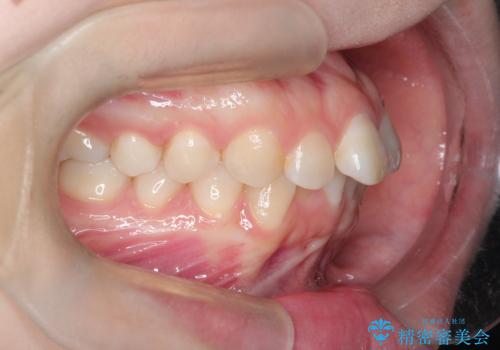

- 前歯のデコボコ(叢生)を気にされてご来院されました。精密な検査の結果、歯が並ぶスペースが不足していることが判明。患者様のご希望から、透明で目立ちにくいインビザライン(マウスピース矯正)による治療計画を立案しました。抜歯を避け、奥歯全体を奥へ動かす遠心移動という方法でスペースを確保し、前歯の叢生を解消することを目指します。

今回の矯正治療では、透明なマウスピース型の装置インビザラインを使用しました。この装置は取り外し可能で、日常生活で目立ちません。治療は、緻密に計算された計画に基づき、段階的に作製されたマウスピースを交換していくことで、奥歯から順に全体を後方へ移動させる遠心移動を実施。これにより、前歯を並べるための十分なスペースが確保され、デコボコが解消されました。抜歯することなく、機能的にも審美的にも整った美しい歯並びを獲得していただけました。